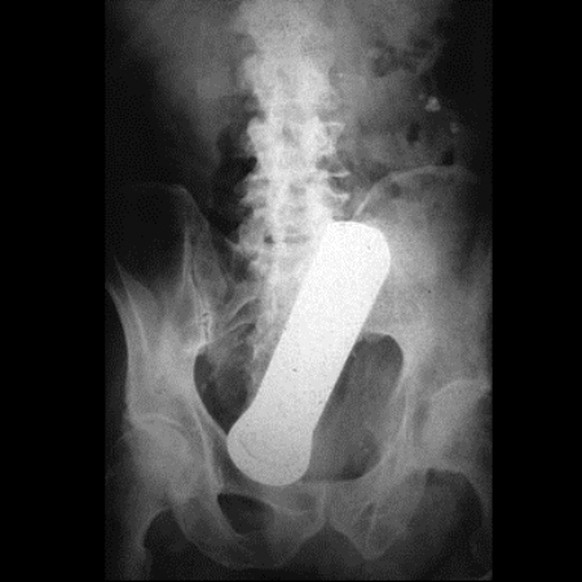

Parfümierter Hintern

Ein 39-jähriger Anwalt kommt zum Arzt, weil er sich ein Parfümfläschchen hinten hinein gesteckt hat. Bevor er sich in die Klinik begab, versuchte er das Fläschchen mit einem Rückenkratzer herauszuangeln – leider erfolglos.